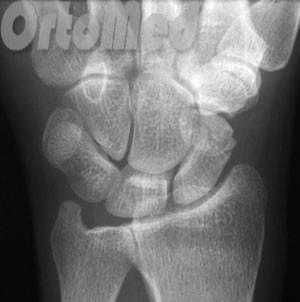

Переломы ладьевидной кости

Любая травма области лучезапястного сустава должна быть оценена врачом травматологом, так как переломы мелких костей могут быть ошибочно расценены пациентом как ушиб. Но последствия перелома ладьевидной кости руки могут быть очень серьезными (см. пояснение в тексте).

Ладьевидная кость является одной из мелких костей запястья. Из всех костей в запястья, переломы ладьевидной кости являются наиболее распространенными. Ладьевидная кость - небольшая кость запястья на стороне большого пальца (с лучевой стороны).

Диагностика переломов ладьевидной кости

Первым и обязательным диагностическим моментом является рентгенография поврежденного участка конечности. Чаще всего рентгенография ясно показывает характер перелома ладьевидной кости.

Если перелом ладьевидной кости происходит без смещения отломков, то линию перелома на рентгенограмме можно и не увидеть. Поэтому очень важно при любой травме кисти выполнить шинирование на 10 дней. На 10 день повторить рентгенограммы кисти и, если перелом все же был, он станет четко просматриваться. Ну а далее выполняют соответствующие лечебные мероприятия (см. раздел лечение переломов ладьевидной кости).